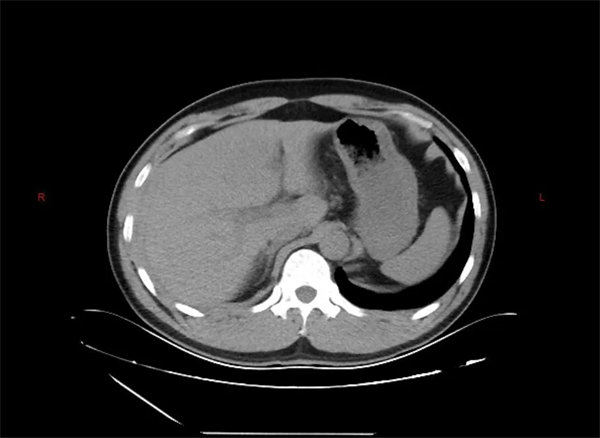

患者为一名中年男性,在工作时不慎被重物砸伤腹部,被紧急送至宝鸡市人民医院急诊科。入院时,患者面色苍白,心率快,腹部有压痛,急诊团队立即为其安排了腹部平扫CT检查。初步CT结果显示:腹腔内存在积血,盆腔有血肿形成,但令人困惑的是,并未发现明显的肝脾破裂直接征象。

通常情况下,肝脾破裂在CT影像上会有相对明确的表现,但此患者的初步影像却呈现“隐匿性”特点。面对这一情况,肝胆胰脾外科主任金上博立即组织科室进行紧急讨论,仔细分析患者伤情与CT影像后,高度怀疑存在活动性出血,且源头很可能就在肝脏。

“虽然平扫CT未见典型破裂征象,但腹腔积血和患者生命体征的变化提示我们,必须进一步明确出血来源。”主管医生在讨论中表示。科室团队当机立断,决定为患者进行急诊增强CT检查。

增强CT犹如为医生装上了“透视眼”,通过对比剂的动态分布,清晰揭示了隐藏在正常肝组织下的破裂伤——患者的肝脏确实存在裂伤,且位置较为隐蔽。这一关键诊断成为后续精准治疗的基础。